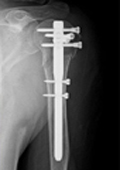

Ist eine Operation erforderlich, wird zur exakten Therapieplanung in der Regel eine Computertomographie durchgeführt. In den meisten Fällen wird eine Osteosynthese mit einer modernen winkelstabilen Platte oder einem Nagel durchgeführt. Manchmal ist auch die Implantation eines künstlichen Schultergelenks erforderlich. In solchen Fällen wird eine Spezialprothese für Frakturen verwendet. In sehr vielen Fällen kann die Osteosynthese mittels winkelstabiler Platte minimal-invasiv über einen nur etwa 4cm langen Schnitt durchgeführt werden.